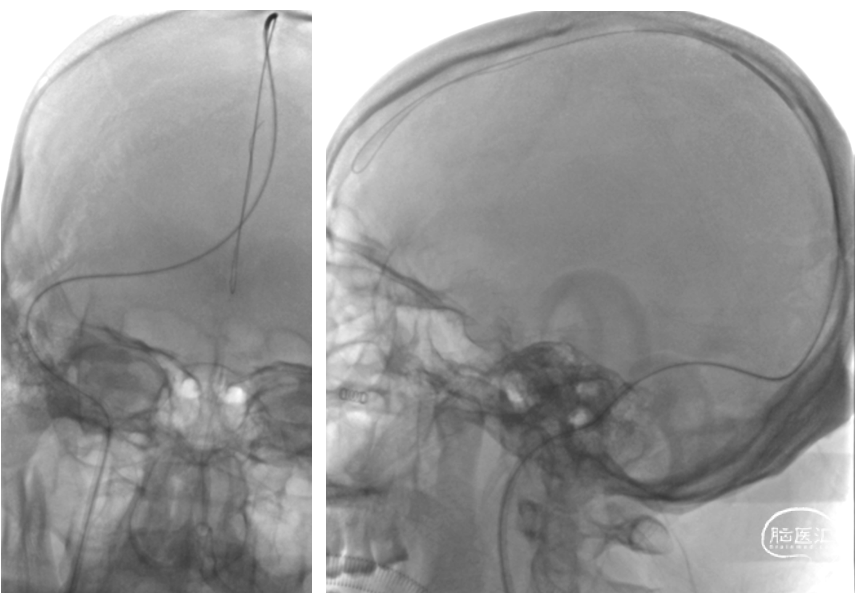

在Transend 300cm微导丝携带下将Wallstent7*40mm支架送至右侧横窦,定位准确后缓慢释放

复查造影右侧横窦显影良好,静脉回流明显改善,乙状窦显影仍欠佳

将Wallstent7*40mm支架沿中间导管送至乙状窦,定位准确后缓慢释放

复查造影:上矢状窦显影明显改善,右侧横窦及乙状窦显影良好,静脉回流良好

颅内正侧位造影:上矢状窦显影明显改善,右侧横窦及乙状窦显影良好,静脉回流良好

在微导丝导引下将Rebar18微导管置于上矢状窦,给予尿激酶25万 单位入50ml生理盐水中,以12ml/h持续微量泵泵入